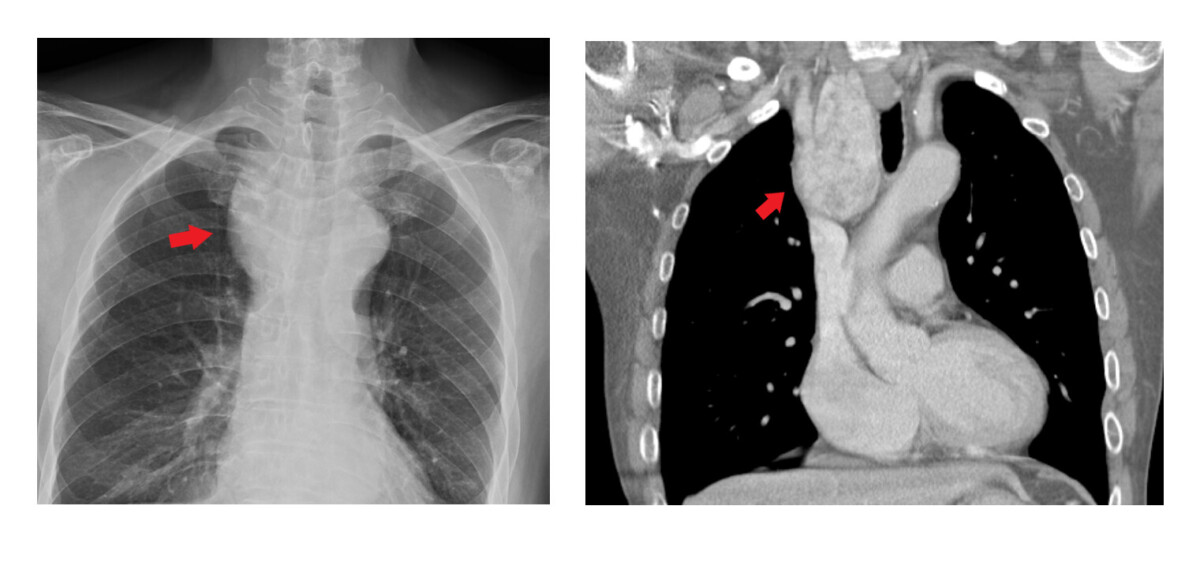

▲左圖為胸部X光,右圖為電腦斷層顯示甲狀腺結節是甲狀腺內部形成的異常組織腫塊,台灣成人盛行率高達40%以上,幸好超過九成以上都是良性的。林晏甥指出,大多數結節位於頸部,但少部分會向下延伸至胸骨後方甚至胸腔內,當結節體積有超過50%位於胸腔,即稱為「胸骨後甲狀腺結節腫大」或「縱膈腔甲狀腺結節」,約占所有甲狀腺手術的3%至17%。

針對一般良性且無壓迫症狀的甲狀腺結節,主要是以超音波與細針穿刺細胞學檢查,由於胸骨後甲狀腺結節腫大位在胸腔內難以用超音波偵測,因此常在有壓迫症狀時才被發現。常見症狀包括呼吸困難、吞咽異物感、聲音嘶啞、慢性咳嗽或喘鳴聲。林晏甥指出,一旦有這些症狀,應儘早就醫檢查,可經由胸部X光及電腦斷層檢查確定診斷。對於胸骨後甲狀腺結節腫大的首選治療方式仍為手術,不僅能緩解壓迫、改善症狀,也能降低惡性變化的風險。